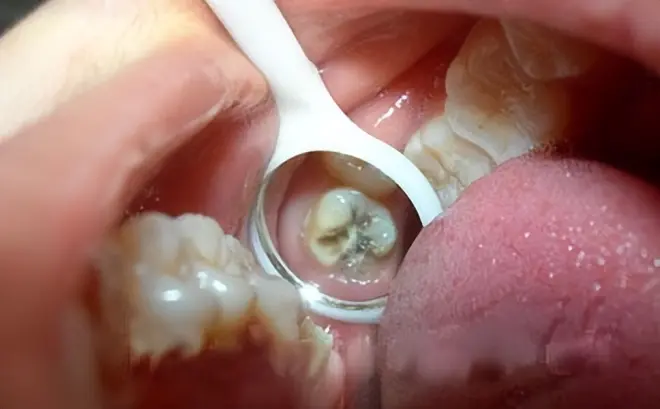

补牙后如果牙体和材料之间又出现了缝隙,表面补牙材料存在脱落的情况,这时很容易有出现继发龋,如果大家有这种情况,要及时就医。

补牙治疗刚完成的时候,如果大家出现了轻微的牙疼,这属于正常情况,但如果牙疼时间过长,甚至扩散到耳朵、头部,可能是补牙材料没有覆盖住牙齿缺损的位置或患上了牙髓炎,这时大家应该及时就医并进行相关复查。

如果牙齿在补牙前缺失的体积比较大,那在做完补牙之后,牙齿也容易断裂,因此我建议大家及时给补过的牙齿佩戴一个烤瓷冠来保护牙齿。